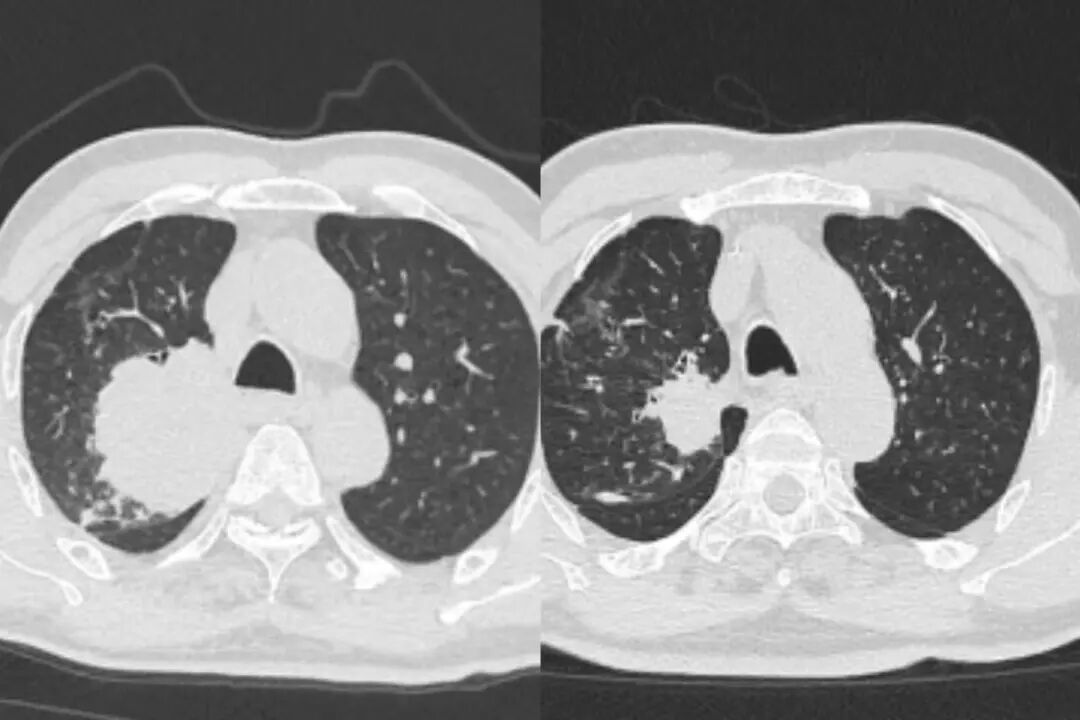

△钱大叔治疗前后CT对比

最终的病理报告带来了最振奋人心的消息,两人的手术标本均达到了pCR,肿瘤细胞已经消失。

实现pCR,可以说是患者治疗的一个重要节点。李剑锋主任表示,这意味着患者不仅获得了根治性手术的机会,术后也大概率无需再进行放化疗,极大地减轻了身心负担,真正实现了高质量的长久生存。